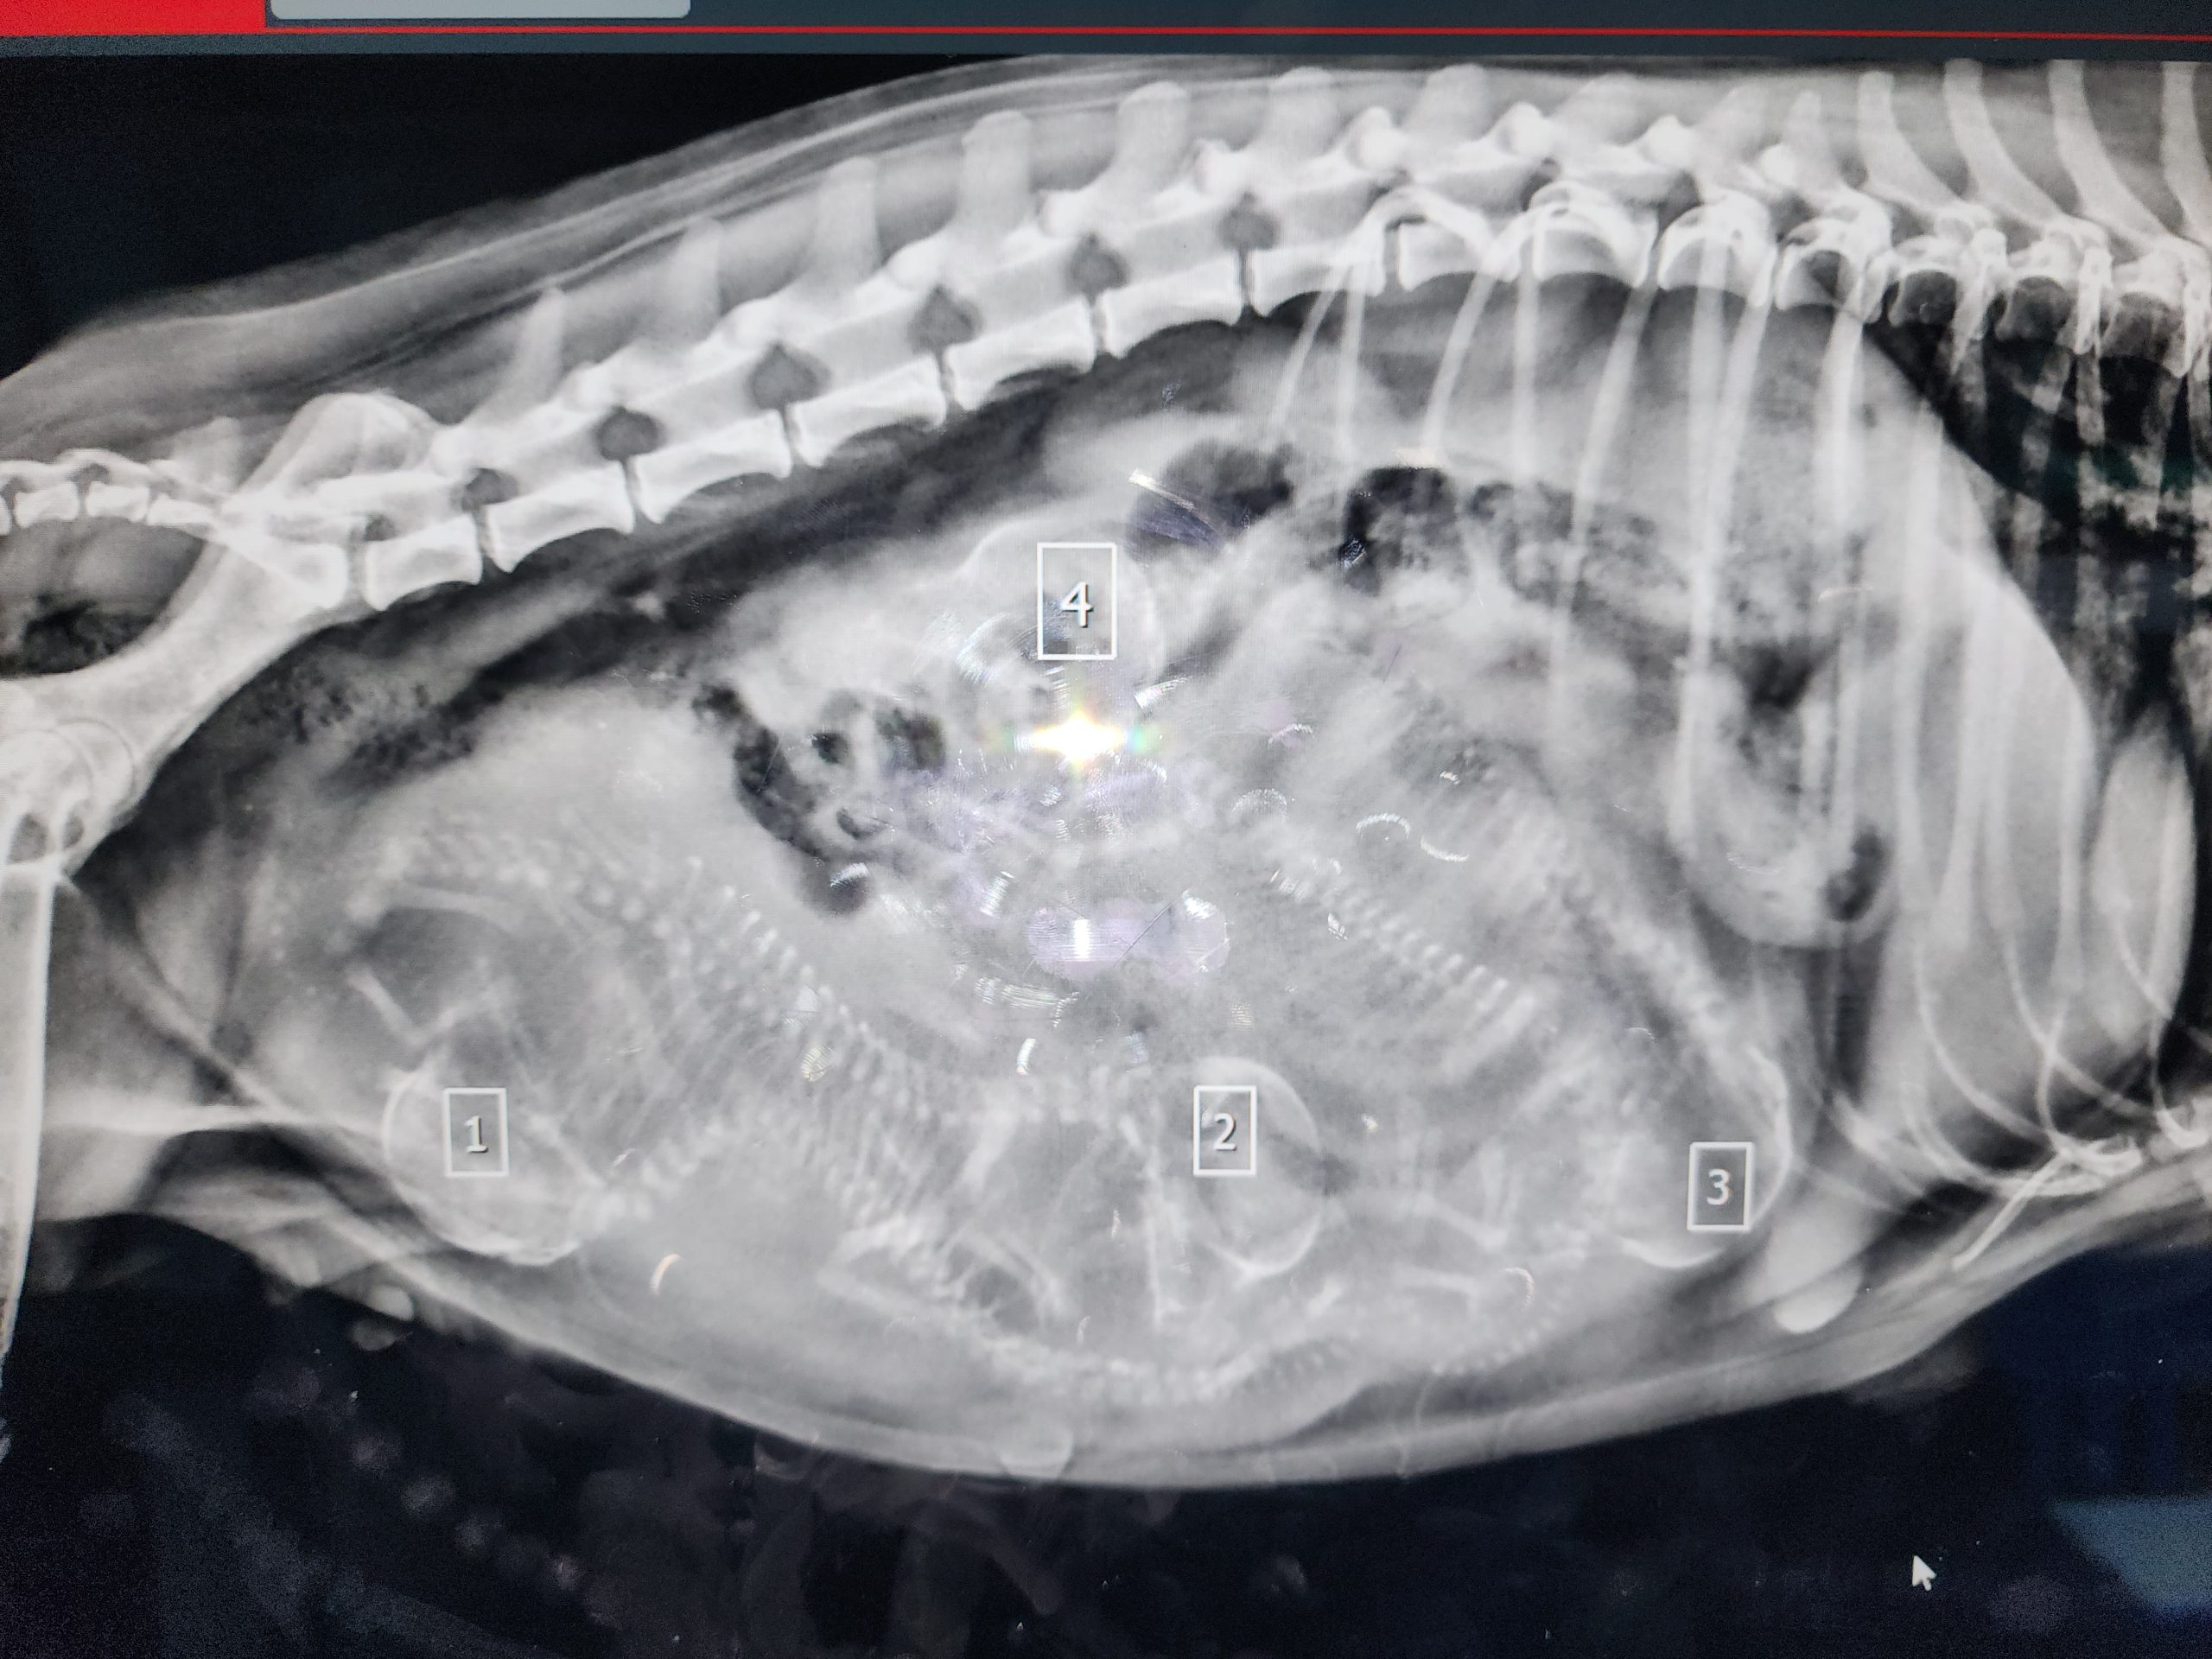

היפוך קיבה אצל כלב